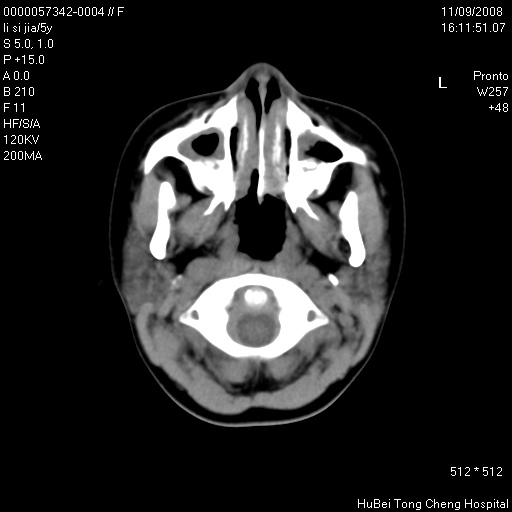

患儿 女,5岁。鼻塞、流涕2年余。

临床诊断:慢性副鼻窦炎?

副鼻窦ct轴位平扫(层厚、层距均为5mm),图像如下:

双侧上颌窦\\筛窦及蝶窦内均可见多量软组织密度影,结合病史支持考虑慢性全鼻窦炎

双侧上颌窦、筛窦及蝶窦内均可见粘膜增厚,结合病史支持考虑慢性全付鼻窦炎,腺样体肥大。